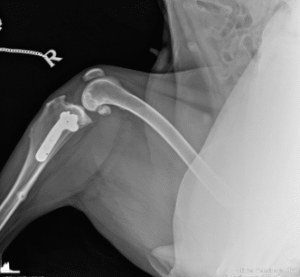

Chirurgia ortopedica

Chirurgia eseguita da specialisti utilizzata per trattare patologie ossee e articolari.

Gli interventi ortopedici sono procedure chirurgiche che trattano patologie dell’apparato muscolo-scheletrico, come fratture, lussazioni, displasie e problemi articolari. Si occupano di correggere deformità, riparare lesioni e migliorare la mobilità degli animali.

Displasia dell’anca: Trattamento chirurgico per correggere questa patologia.